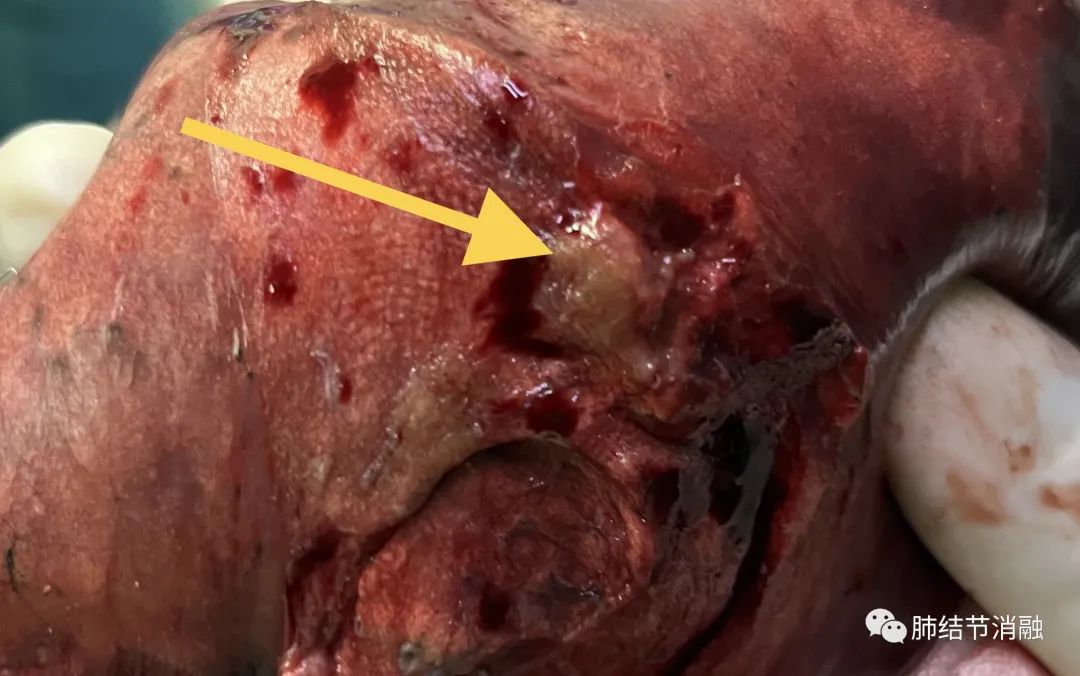

主病灶染色区域

手术切除8毫米主病灶